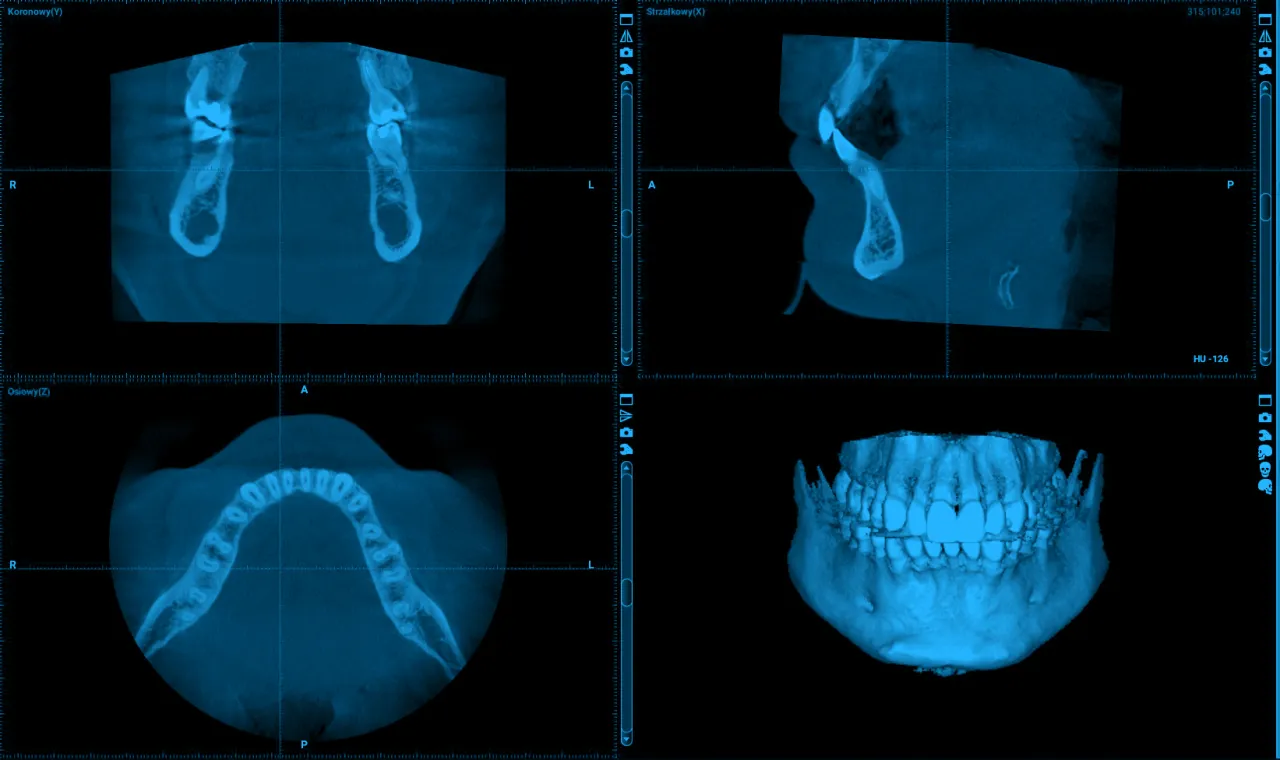

Pantomogram, mimo że przez lata był podstawowym narzędziem do oceny całego uzębienia i kości szczęki oraz żuchwy, ma swoje ograniczenia. Jest to zdjęcie panoramiczne, które daje nam ogólny zarys, ale często nie pozwala na dostrzeżenie subtelnych zmian. Wyobraźmy sobie, że próbujemy ocenić stan budynku, patrząc tylko na jego fasadę możemy przeoczyć problemy konstrukcyjne w głębi. CBCT działa zupełnie inaczej. Aparat wykonuje serię setek zdjęć pod różnymi kątami, które następnie komputer składa w precyzyjny, trójwymiarowy model. Dzięki temu możemy "przekroić" badany obszar w dowolnej płaszczyźnie, analizując go warstwa po warstwie. To pozwala na dokładniejszą ocenę anatomii, wykrycie nawet niewielkich zmian patologicznych, które na płaskim zdjęciu byłyby po prostu niewidoczne lub maskowane przez inne struktury. Ta szczegółowość jest nieoceniona w kontekście precyzyjnego planowania leczenia.

Kiedy pacjent pyta mnie, co właściwie pokazuje tomografia komputerowa zęba, zawsze staram się to wyjaśnić w sposób zrozumiały. Obraz 3D z CBCT jest niezwykle bogaty w informacje i pozwala na szczegółową analizę struktur, które w dwuwymiarowym świecie RTG pozostają ukryte lub niedokładnie odwzorowane. To właśnie ta wszechstronność sprawia, że badanie to jest tak cenne w codziennej praktyce stomatologicznej.

Na obrazie 3D możemy zobaczyć ząb z niespotykaną dotąd precyzją. Analizujemy nie tylko koronę, ale przede wszystkim korzenie ich liczbę, kształt, długość i wszelkie zakrzywienia. To kluczowe w leczeniu kanałowym, gdzie nawet drobne odchylenia od normy mogą stanowić wyzwanie. CBCT pozwala nam precyzyjnie zlokalizować i ocenić przebieg, szerokość, a nawet obecność dodatkowych, nietypowych kanałów korzeniowych, które często są przyczyną niepowodzeń w leczeniu. To jak posiadanie trójwymiarowego schematu całego systemu korzeniowego, co jest nieocenione dla skuteczności terapii.

Kość szczęki i żuchwy to fundament, na którym opierają się nasze zęby. Tomografia CBCT pozwala nam ocenić jej stan z niezwykłą dokładnością. Analizujemy gęstość, wysokość i szerokość kości w konkretnym obszarze. To informacje absolutnie kluczowe, zwłaszcza w przypadku planowania leczenia implantologicznego, gdzie musimy mieć pewność, że kość jest wystarczająco mocna i obszerna, aby utrzymać implant. Ponadto, CBCT pomaga nam wykryć i ocenić ubytki kostne spowodowane chorobami przyzębia, co jest niezbędne do zaplanowania odpowiedniego leczenia periodontologicznego.

Zakres możliwości CBCT wykracza daleko poza sam ząb i jego bezpośrednie otoczenie. Badanie to pozwala nam również ocenić stan zatok szczękowych, co jest istotne, gdy planujemy zabiegi w górnej szczęce, na przykład podniesienie dna zatoki. Możemy precyzyjnie zlokalizować ważne struktury nerwowe, takie jak nerw zębodołowy dolny, co jest kluczowe dla bezpieczeństwa podczas zabiegów chirurgicznych w żuchwie. Ponadto, CBCT umożliwia dokładną wizualizację budowy stawów skroniowo-żuchwowych, pomagając w diagnostyce ich dysfunkcji i schorzeń. Te dodatkowe informacje są niezwykle cenne dla kompleksowej opieki nad pacjentem.